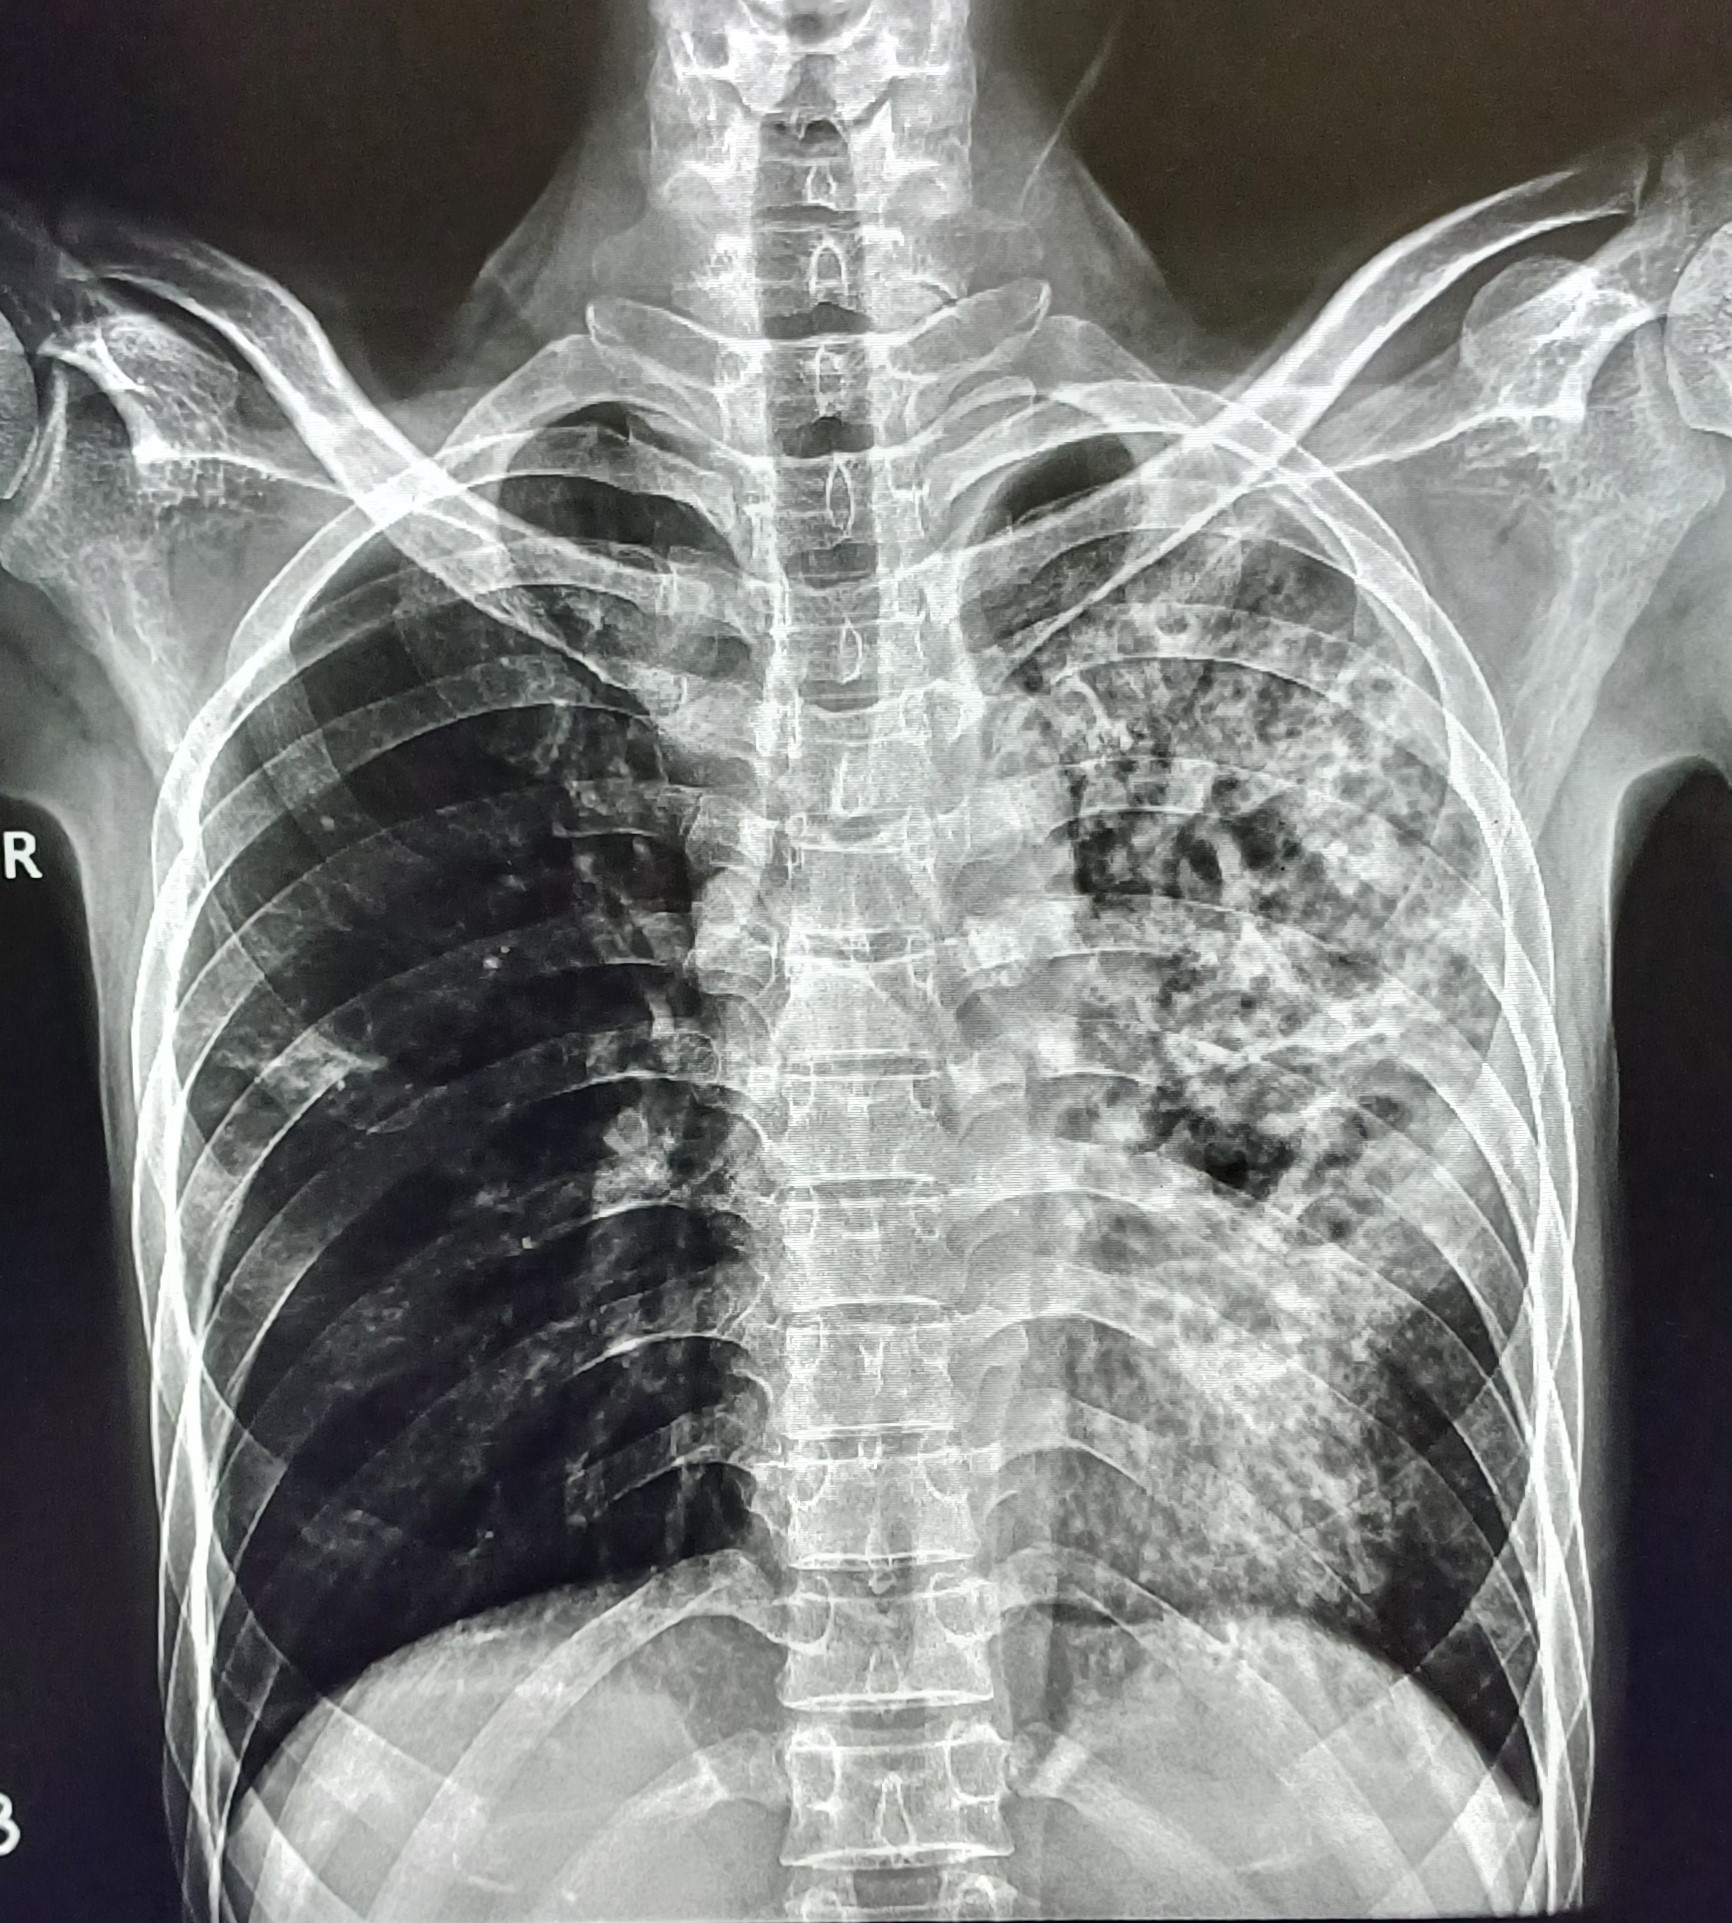

| 5 | IGGMC, Nagpur, Nagpur | P2 | 29-4467 | Meera Gohare | Consent taken on Paper | 64 Yrs. |

Provisional Diag : ?

Final Diag : Disseminated TB (Miliary TB With Abdomen Koch) |

TB Case (Confirmed) | Abnormality visible on x-ray |

View |

||||